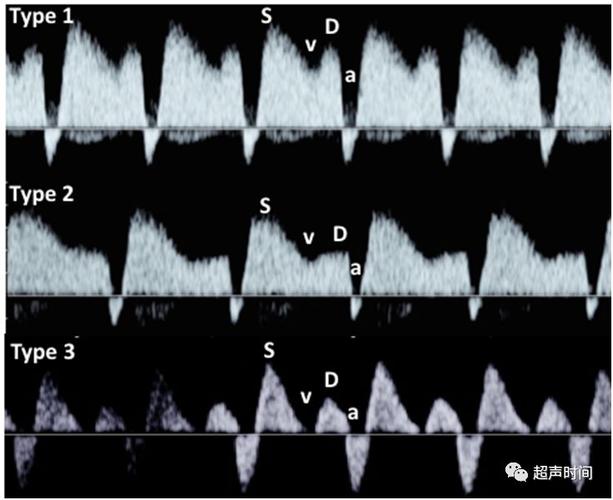

胎儿静脉导管血流频谱

正常静脉导管频谱图